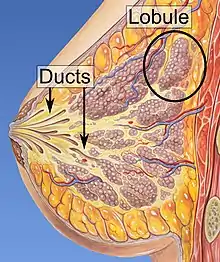

Risk factors for developing breast cancer include obesity, a lack of physical exercise, alcohol consumption, hormone replacement therapy during menopause, ionizing radiation, an early age at first menstruation, having children late in life or not at all, older age, having a prior history of breast cancer, and a family history of breast cancer.[1][2][9] About 5–10% of cases are the result of an inherited genetic predisposition,[1] including BRCA mutations among others.[1] Breast cancer most commonly develops in cells from the lining of milk ducts and the lobules that supply these ducts with milk.[1] Cancers developing from the ducts are known as ductal carcinomas, while those developing from lobules are known as lobular carcinomas.[1] There are more than 18 other sub-types of breast cancer.[2] Some, such as ductal carcinoma in situ, develop from pre-invasive lesions.[2] The diagnosis of breast cancer is confirmed by taking a biopsy of the concerning tissue.[1] Once the diagnosis is made, further tests are done to determine if the cancer has spread beyond the breast and which treatments are most likely to be effective.[1]

- Histopathology. Breast cancer is usually classified primarily by its histological appearance. Most breast cancers are derived from the epithelium lining the ducts or lobules, and these cancers are classified as ductal or lobular carcinoma. Carcinoma in situ is growth of low-grade cancerous or precancerous cells within a particular tissue compartment such as the mammary duct without invasion of the surrounding tissue. In contrast, invasive carcinoma does not confine itself to the initial tissue compartment.[135]